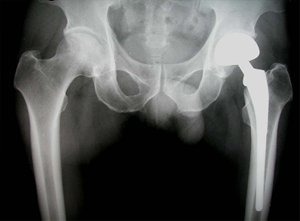

상기 환자는 46년 전부터 고관절 통증이 있었으며, 12년전 Lt. total hip replacement(THR)을 받은 분으로 2년 전부터 통증으로 인해 물리치료를 받았지만 통증이 지속되었고, 본원 OS 외래에서 방사선 촬영하여 Lt. THR loosening 소견으로 revision O.P. 위해 입원하여 O.P.이후 재활위해 물리치료실로 의뢰됨

고관절 치환술 후 X-선 사진